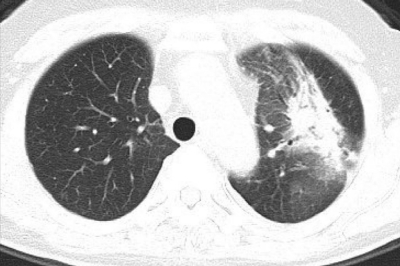

血液所見:赤血球 389 万、Hb 10.2 g/dL、Ht 32 %、白血球 5,800、血小板 25 万。血液生化学所見:総蛋白 6.7 g/dL、アルブミン 3.7 g/dL、総ビリルビン 0.3 mg/dL、AST 16 U/L、ALT 13 U/L、LD 273 U/L (基準 176〜353) 、クレアチニン 0.9 mg/dL、Na 143 mEq/L、K 4.4 mEq/L、Cl 105 mEq/L、CEA 4.8 ng/mL(基準5以下)。CRP 1.3 mg/dL。胸部エックス線写真と肺野条件の胸部CTとを別に示す。

最も考えられるのはどれか。

b. 放射線肺炎